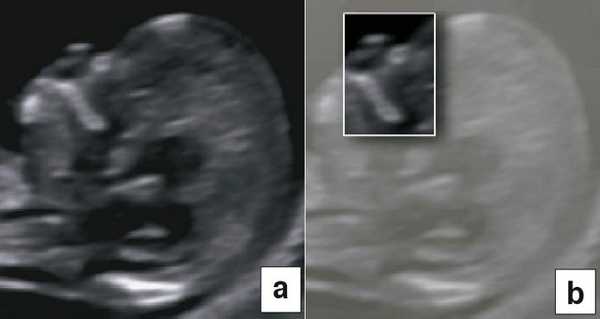

Диагноз хориальности и количества амнионов

УЗИ при двойне в основном должно выявить хориальность (ди- или монохориальность) и для монохориальных беременностей (моно- или диамниотических) - количество амнионов. При многоплодной беременности эта информация необходима для соответствующего ведения дискордантной мальформации, замедления роста, внутриутробной гибели плода или получения образцов ткани плода. Точность этой диагностики в течение I триместра может достигать 100%, а затем на протяжении беременности она уменьшается [7]. Дихориальность подтверждают выявлением лямбда-признака (рис. 4a). Наоборот, монохориальность диагностируют при отсутствии визуализации лямбда-признака или выявлении T-признака (рис. 4b) в межамниотической мембране, расположенной перпендикулярно хорионической пластине.

Рис. 4. Диагностика хориальности и количества амнионов в I триместре путем оценки лямбда-признака (a) и T-признака (b).